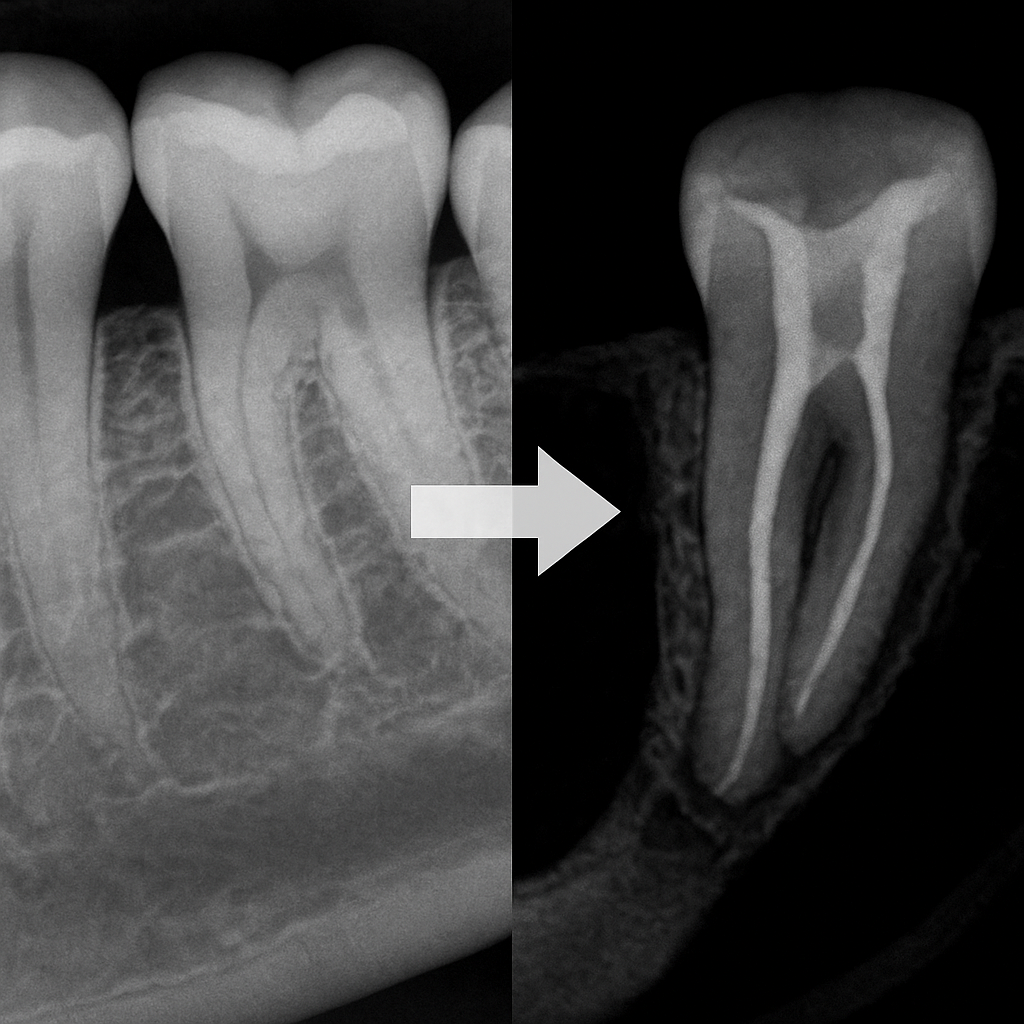

КЛКТ vs Прицельный снимок

Почему в эндодонтии важно использовать КЛКТ, а не только прицельный снимок.

Прицельный снимок показывает зуб в проекции, искажение всегда присутствует.

КЛКТ даёт объемное изображение, позволяя увидеть:

скрытые дополнительные каналы (MB2, извитые, слияния),

степень кривизны и её направление,

истинную толщину стенок и риск перфорации,

состояние периапикальных тканей в динамике,

резорбции, трещины и скрытые очаги.

По данным исследований, до 35–40% анатомических особенностей корневых каналов остаются незамеченными на обычном рентгене, что напрямую увеличивает риск ошибки на первом же этапе лечения.